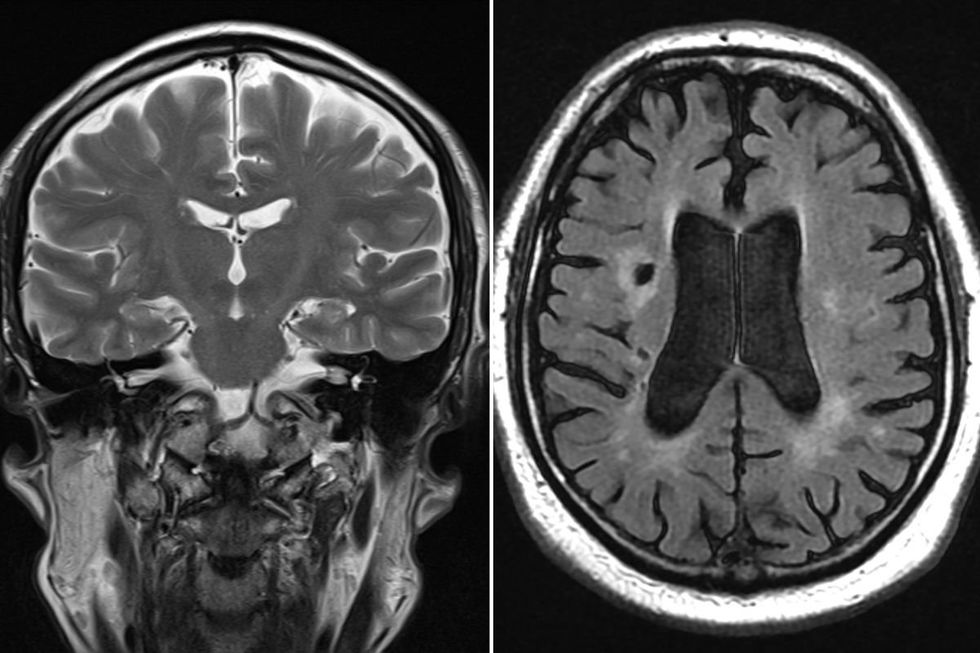

A Scottish man is encouraging others to learn about the lesser-known warning signs of stroke after his only symptom was a sudden inability to read.

Gordon Robb, 63, from Bonnyrigg in Midlothian, experienced a brain bleed that left him unable to make sense of written words.

Emails, text messages, and even cash machine displays suddenly looked as though they were written in an entirely different language.

This particular symptom is incredibly rare. Specialists say that struggling to recognise written words alone, without any other signs, happens in fewer than 1 per cent of stroke patients.

When it comes to reading difficulties, as Mr Robb experienced, Lowe explains this happens when a small, specific area of the brain is affected, disrupting what experts call "higher executive functioning."